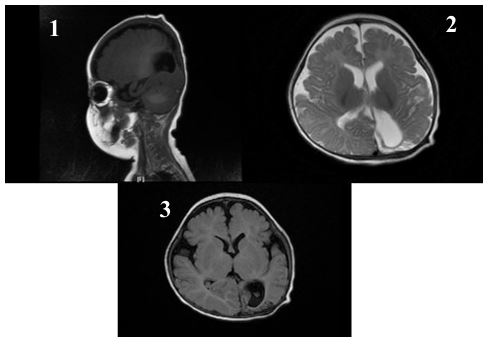

After 11 days of treatment, physical examination revealed mild swelling and redness in the posterior fontanelle area at the midline and slightly to the left of the occipitoparietal region, ap proximately 3 cm in diameter, soft in texture with slight fluctua t ion. The brain enhanced MRI showed abnormal enhancement signals in the right parietal lobe and the left parieto-occipital area, suggesting an infectious lesion. Brain tissue was under compression and midline shift were observed (Figure 1). After the child was diagnosed with brain abscess, he was transferred to the neurosurgery department for further treatment. The sur gery of brain abscess drainage and external subdural effusion drainage was performed under general anesthesia with tracheal intubation. During the operation, a cyst infection was observed, and it eroded the underlying dura mater, with tight adhesion between the cyst wall, brain tissue, and dura mater surrounding the dura mater, thickening of the dura mater, and necrosis of the surrounding brain tissue. The infected cyst wall was separated from the surrounding dura mater, carefully dissected from the lateral to the midline to the brain tissue interface, with protec t ion of the sagittal sinus at the midline, and deep erosion of the falx cerebri. The infected cyst had broken through to the oppo site side. The right dura mater was incised, and the infected cyst and necrotic brain tissue were thoroughly removed, connecting both sides. The defected skull was about 1x3 cm in size (Figure 2). Infected DSTs and ruptured DCs with parieto-occipital brain abscess were resected (Figure 3). Postoperative pathological examination showed that purulent inflammation with abscess formation was formed. After surgery, the child was treated with meropenem (0.2 g Q8H 21d) and linezolid (0.05 g Q8H 21d) to resist infection. The child recovered smoothly after surgery, and follow-up showed good growth, with no recurrence or neuro logical sequelae (Figures 4 & 5).

Figure 4: One-month postoperative follow-up examination. (1) Abnormal signals in the right parietal and left parieto-occipital lobes decreased in size, with partial softening and gliosis. (2) Bilateral parietal short T1 signals slightly decreased. (3) Minor left frontotemporal subdural effusion decreased from previous; bilateral frontotemporal epidural space slightly widened.